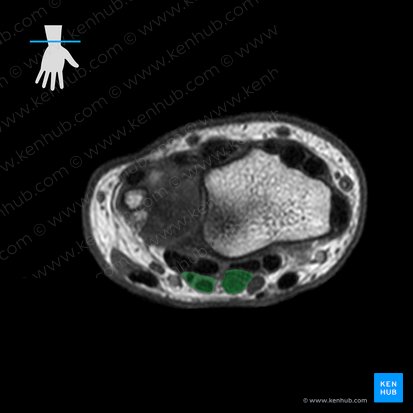

Tendons and carpal tunnel

If you compare the MRI images of the proximal and distal limits of the radiocarpal joint, you will see two major differences; the latter contains no actual muscles but showcases the important carpal tunnel and ulnar canal. The arrangement of the tendons at this axial level stays almost identical to the previous one. The only exception is the extensor pollicis longus tendon which is now located on the radial aspect of the extensor carpi radialis brevis tendon. This is because the tendon of extensor pollicis longus has a more pronounced trajectory towards the thumb compared to its neighbour.

The carpal tunnel is a passageway between the distal forearm and hand. It consists of a base, two walls and a roof. The base and walls are formed by the distal row of carpal bones while the roof is represented by the flexor retinaculum of the wrist. The carpal tunnel contains the median nerve and nine tendons; one of flexor pollicis longus, four of flexor digitorum profundus and four of flexor digitorum superficialis. The carpal tunnel is located on the palmar aspect of the wrist, in the midline. All ten structures passing through it are visible at this MRI level. They appear as aggregated hypointense circles surrounded by grey soft tissue. The tendons are layered identically to their muscular counterparts observed in the first axial MRI image.